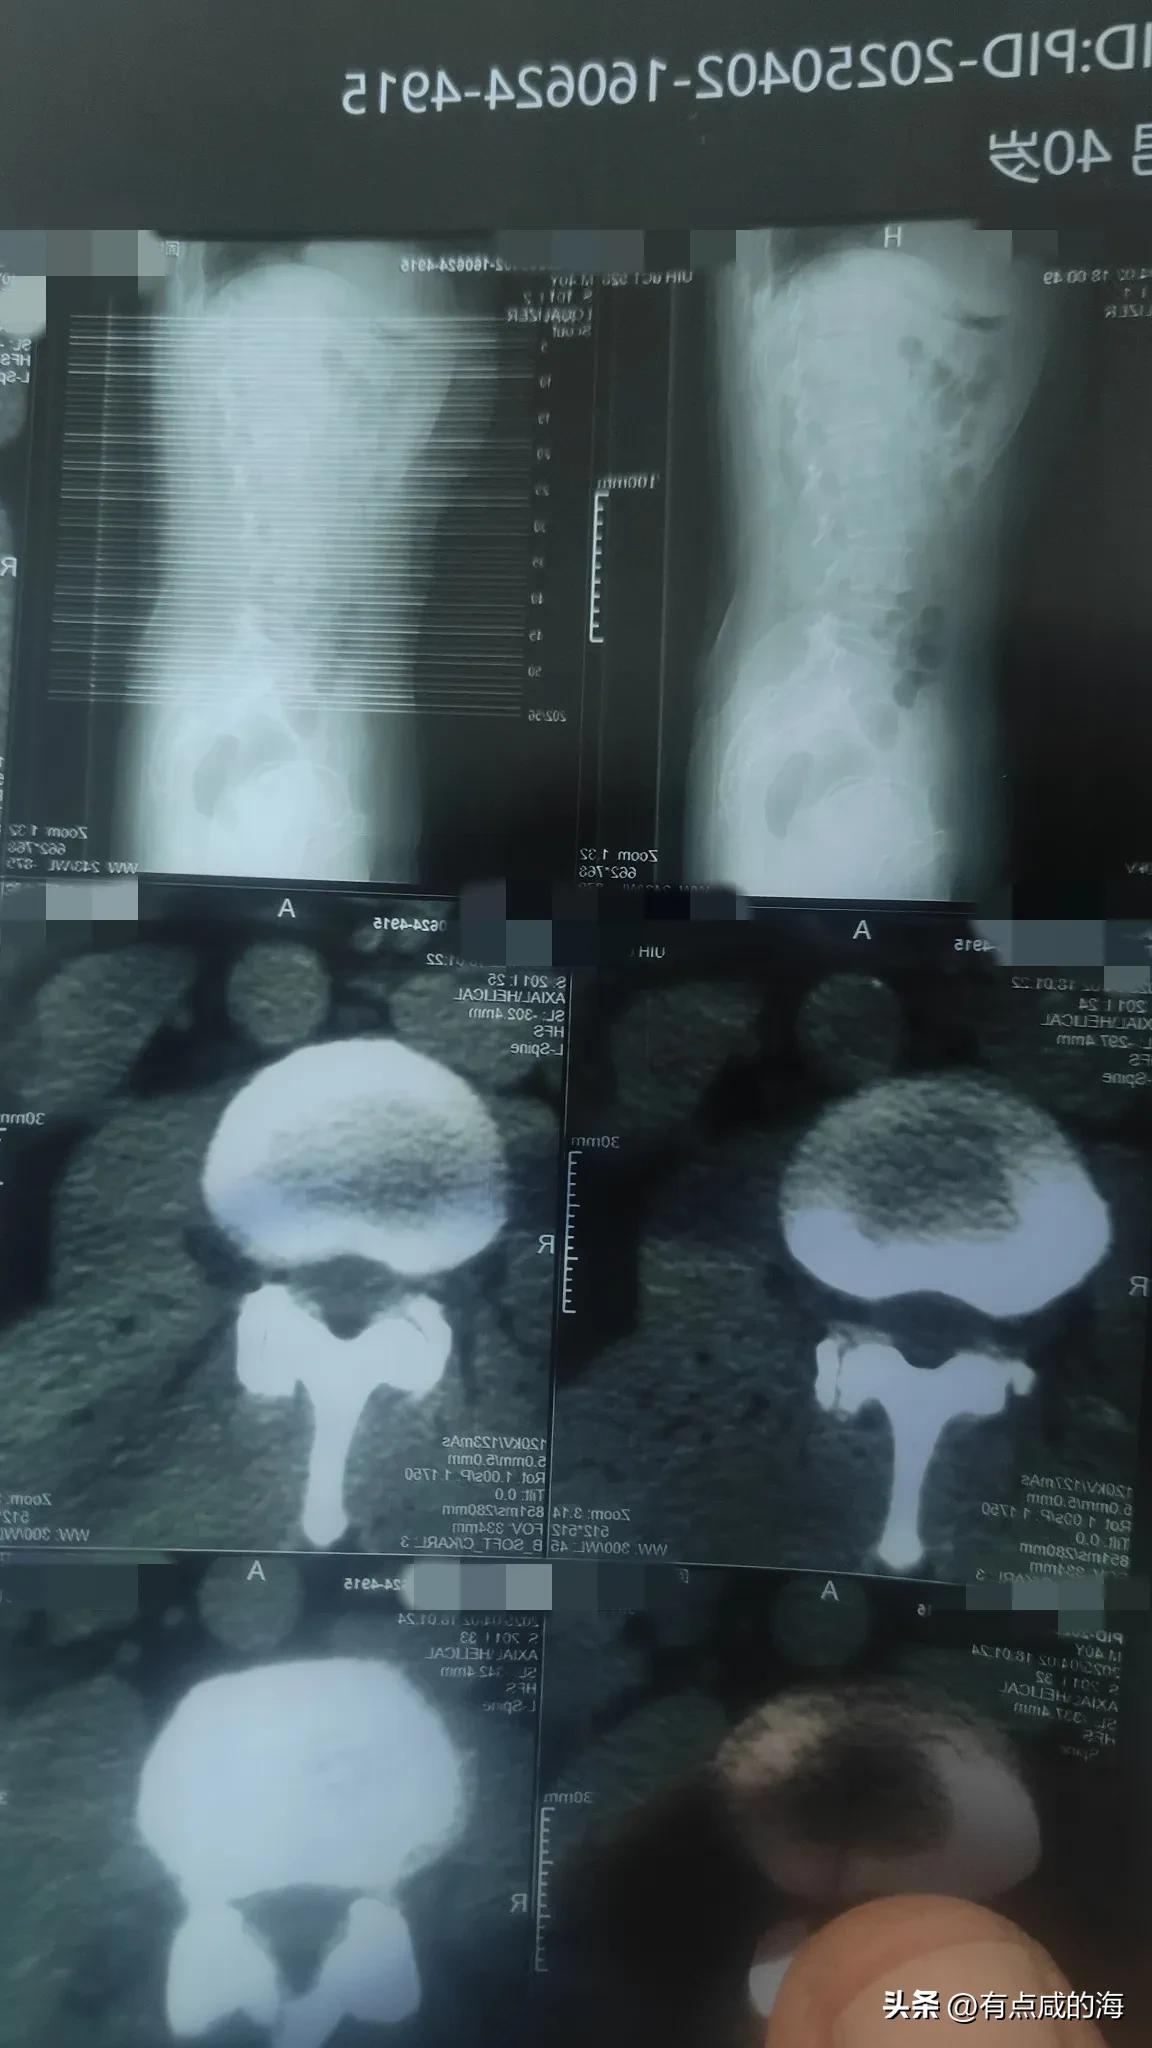

哪位大哥大姐给看看片子,刚拍的 说有点腰间盘突出,还说有个肾结石,花生米大小,现